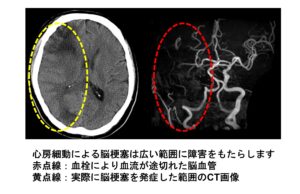

心房細動における抗凝固療法(血液サラサラ)の意義

各種報道などで心房細動の併発症としての心原性脳塞栓症予防の意義はかなり知られるようになりました。そこで、一般の方に知っておいてほしい知識について簡単にまとめたいと思います。 ✓高血圧、糖尿病、高尿酸…